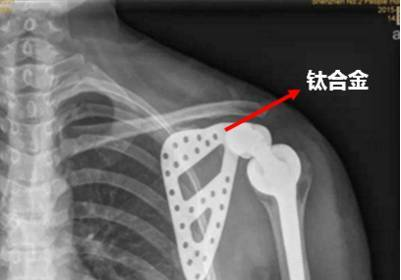

但是现有的研究结果表明,纯的羟基磷灰石虽然具有优良的生物相容性与生物活性,但力学性能较差,不能用作承重植入材料。而另一种骨替代材料医用钛及钛合金材料,虽然具有优良的力学性能,但耐磨性差、同时属于生物惰性材料,与骨的结合是一种机械锁合。

有鉴于此,在医用钛及钛合金表面制备羟基磷灰石生物陶瓷涂层是目前国内外的研究热点,具有重要的理论及实践意义。

以钛合金为基底,利用等离子喷涂技术制备的羟基磷灰石涂层,涂层与基底结合强度高,该材料植入人体后,钛合金可以提供足够的力学强度,表面的羟基磷灰石涂层易于与人体骨结合,在人体骨表面诱导新骨的生成,一般数月即可诱导新骨的生成。但在体内植入后出现涂层脱落的现象还有待进一步研究。